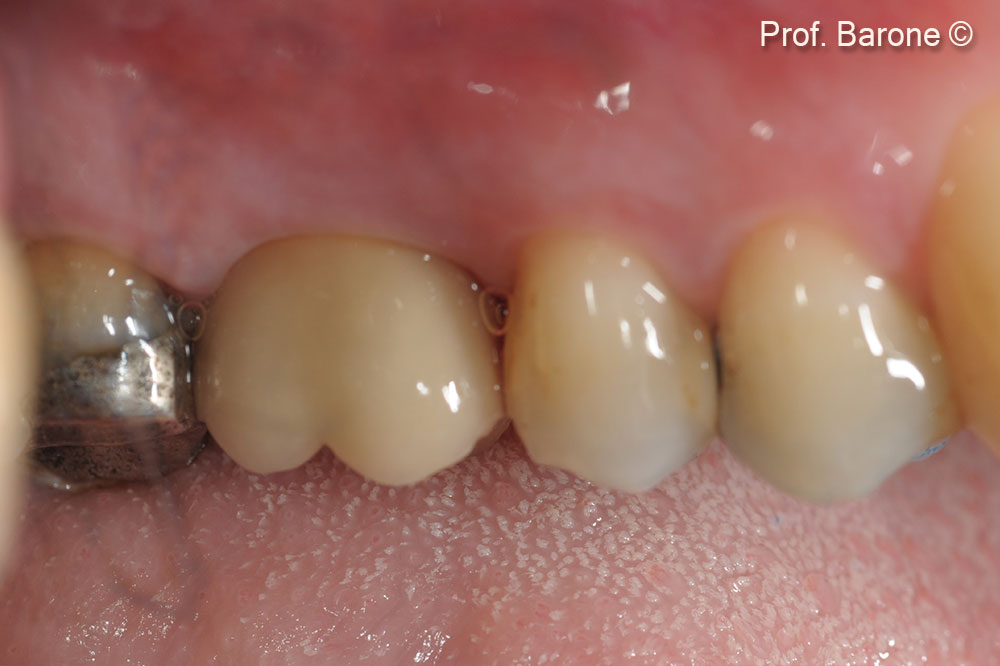

Phục hình cuối cùng sau 3 năm theo dõi.